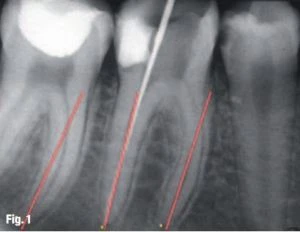

Nhìn vào hình ảnh giải phẫu của ống tủy, điều đầu tiên có thể thấy là chúng luôn lệch khỏi trục dài chân răng và lỗ chóp hầu như không bao giờ trùng với trục chính của chân răng (Hình 1). Những chi tiết giải phẫu và những biến thể của vùng chóp là điểm cốt yếu để quyết định WL.

Hình 1: Lỗ chóp hầu như không bao giờ trùng với trục chính của chân răng.